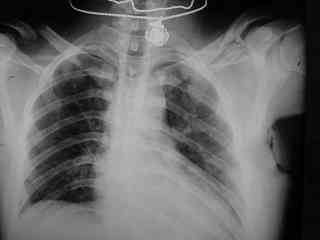

C> Postupil ko mne bolnoi s perelomom obeih kluchits, neznachitelny

C> pneumotorakx sleva.

Ну а за пневматораксом надо вести наблюдение, рентгенконтроль. При необходимости дренировать плевральную полость.

С пневмотораксом все понятно-дренировать плевральную польсть. А вот на счет ключиц действительно вопрос интересный, необходима золотая середина. Учитывая, что имеется повреждение грудной клетки, для улучшения активного дыхания необходимо будет выполнить остеосинтез обеих ключиц, накостный, реконструктивными пластинами.

Bolnogo operirovali plastinami, snimky zdes'.

CIMG1145.JPG

Похоже, все прошло по плану. Поздравляю с успешной операцией!

Pneumatorax hirurg punctiroval i lechil dalshe, operasia zanimala 1 chas 35 minut, ni bilo problem ossobih.